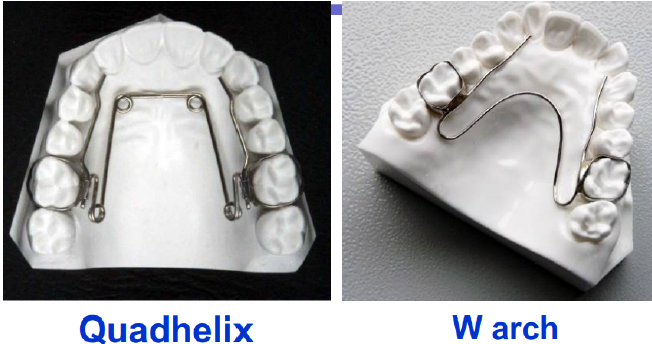

palatal expansion: RPE, SPE

一轉 0.25mm a

-

RPE: 一天兩轉

-

SPE: 兩天一轉